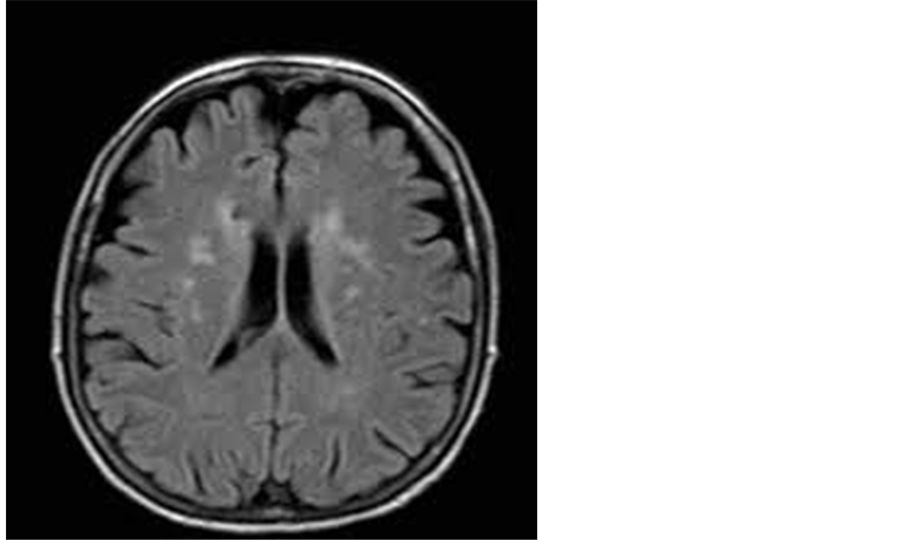

Demographic: With regards to gender, 60 patients (75%) were male and 20 patients (25%) were female. The mean group age was 42.4 years. Criteria and distribution of MRI brain lesions are described in Table 1, Figure 1, Figure 2 and Figure 3.

From the table we noticed that 50% of cases (24/48) had silent cerebral infarctions with periventricular white matter distribution, 33.3% (16/48) had infarcts in the basal ganglia and 16.66% had infarction in the thalamus.

Figure 1. A 51-year-old male patient with multiple periventricular lacunar infarctions of high FLAIR signal.